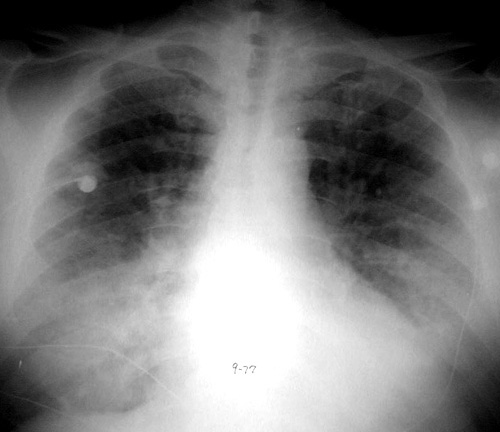

Diffuse Alveolar Hemorrhage

Acute onset bilateral airspace disease due to hemorrhage in a patient with Wegners granulomatosis.